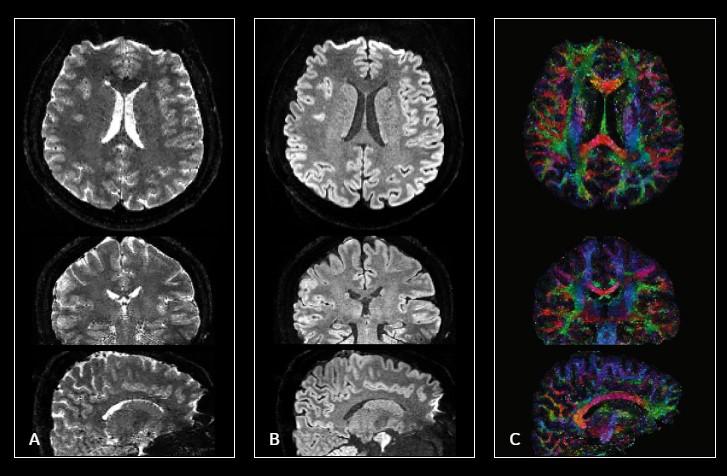

Effects of Lifelong Musicianship on White Matter Integrity and Cognitive Brain Reserve

Manuscript titled "Effects of Lifelong Musicianship on White Matter Integrity and Cognitive Brain Reserve” has been published in "A Decade of Brain Sciences." Duke co-authors were E. Andrews, C. Eierud, D. Banks, T. Harshbarger, and A. Michael.

Influence of Structural and Functional Brain Connectivity on Age-Related Differences in Fluid Cognition

Manuscript titled "Influence of Structural and Functional Brain Connectivity on Age-Related Differences in Fluid Cognition” has been published in Neurobiology of Aging. BIAC co-authors were D. Madden, S. Jain, A. Cook, H. Huang, and J. Cohen.